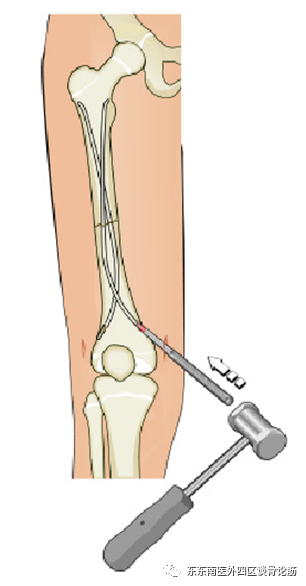

评估病情后,我科运用闭合复位弹性髓内针固定的微创技术对涛涛进行了手术治疗,将其断骨接上了。弹性髓内针可以做到闭合置钉,不仅可达到良好复位及良好固定的基本要求,还具有小切口微创置入,骨折处无需切开,对血供影响小,不破坏骨膜,不损伤神经,利于骨痂生长,完全符合儿童生理。这一微创治疗方式有效地降低了因手术创伤影响儿童骨折生长发育的风险。

(术前标记进针点)

(C臂X光机引导下闭合复位穿针)